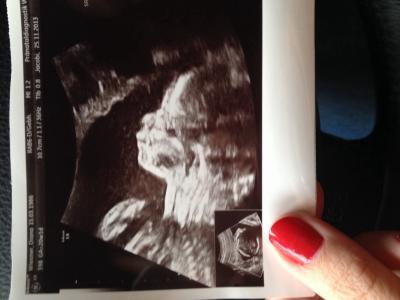

Bin auch mal wieder da. Hoffe es geht euch gut. Habe ein aktuelles Bild von der Feindiagnostik beigefügt Habe jetzt mal gesehen dass am 11.12. schon mein GV Kurs anfängt. Da bin ich gerade mal 23. ssw. Das wird peinlich naja später war nichts mehr frei:-/ Fängt noch jm so früh an? Lg Maja

Bild zu Huhuuuu - Forum für April - Mamis

lieber früher ich hab erst so spät bekommen fang erst 30 ssw an... lg PS: süß dein Zwerg hab am montag 3D freu mich auch schon riesig darauf.

tolles Bild! schön das alles prima ist! ich fange erst im Februar an, sind aber auch nur fünf Termine. ich finde das gar nicht so schlecht. man lernt da ja zum Teil auch ganz liebe andere Leute kennen. meine letzte hebi hat ihre Termine immer so komisch angeboten das zum Schluß schon die Hälfte entbunden hatte. ist ja auch nicht Sinn und Zweck der Sache :-D

Wow was für ein Bild! Krass wie gut man da alles erkennen kann!!!

Hey so ein süßes Bild! Wahnsinn das man das soooo gut erkennen kann. So süß! Hach ich hab den Kurs erst 29-30 März könnte knapp werden, falls die Prinzessin schon früher raus will^^ Naja mal schauen. Aber bei uns geben sie die Kurse immer erst 2 Wochen vor der Geburt....